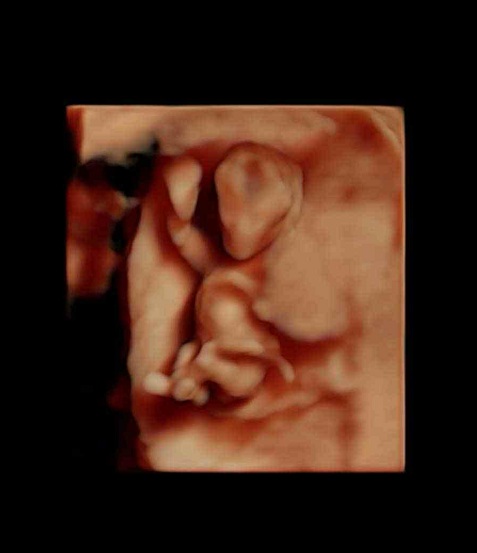

三维图

胎儿发育

本周已能够清晰地看到胎儿脊柱的轮廓,脊神经开始生长。你的子宫现在看起来象个柚子,借助多普勒仪器,你可以听到胎儿心脏快速跳动的声音,有些孕妇称之为快速奔跑的小马。

胎儿身长已经达到4-6厘米,体重达到14克,开始能做吸吮、吞咽和踢腿动作,在本周胎儿的很多细微之处也开始出现,可清晰的看到手指、脚趾和绒毛状的头发等。胎儿维持生命的器官如肝脏、肾、肠、大脑以及呼吸器官都已经开始工作。